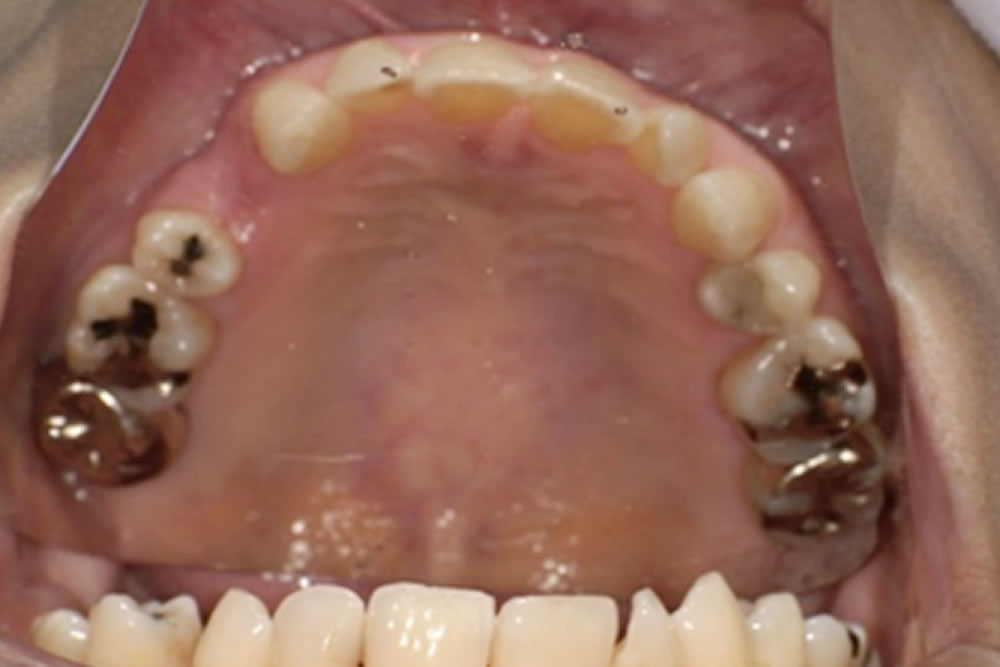

次にブリッジ治療も検討されましたが、欠損部の両隣の歯を大きく削って土台にする必要があります。今回の症例では犬歯が支台歯となるため、横方向の力が強く加わり歯根に大きな負担がかかること、また支台となった歯の寿命を縮める可能性があることから、長期的なリスクを十分に説明し、慎重に検討しました。固定式で違和感が少ないという利点はあるものの、清掃が難しく、支台にした歯の状態が悪化すればブリッジ全体の作り直しが必要になる点など、将来的な負担を考えると適応は慎重になる必要がありました。

義歯の設計では、口腔内の形態に合わせて、床の前方を小さく・後方を大きめにするなど細かな工夫を行い、装着時の違和感が少しでも軽減されるよう調整しました。